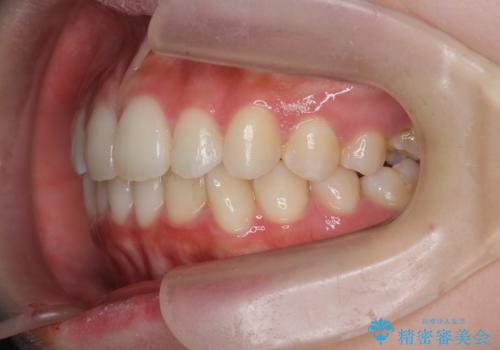

インビザラインライトで行う短期マウスピース矯正治療

- 前歯のガタつきを並べたいたいと、矯正治療を希望され来院されました。

とにかく短期間で前歯だけの治療を行いという希望が強く、全体矯正と前歯だけの部分矯正の仕上がりのイメージを確認したのち14枚のマウスピースで前歯のみの矯正治療を行っていくこととしました。

インビザラインライトは軽度なガタつきや傾斜の改善に用いられる全14枚のマウスピース矯正です。